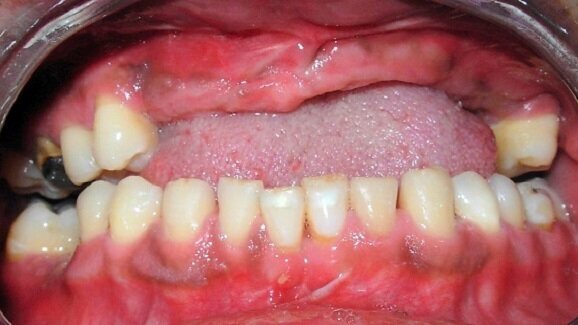

Using stem cells is also a better solution than dentures, which some patients find uncomfortable or fixed titanium implants, which “create a totally artificial situation,” Yelick says.

Because an implant can’t move, the repeated impact of chewing is transferred directly to the jawbone and surrounding teeth, causing gradual bone loss. “If you could instead implant living, vascularized tooth in the jaw, that could be a much better option,” says Yelick, who also holds faculty appointments at the Sackler School of Graduate Biomedical Sciences, the School of Medicine and the School of Engineering at Tufts.